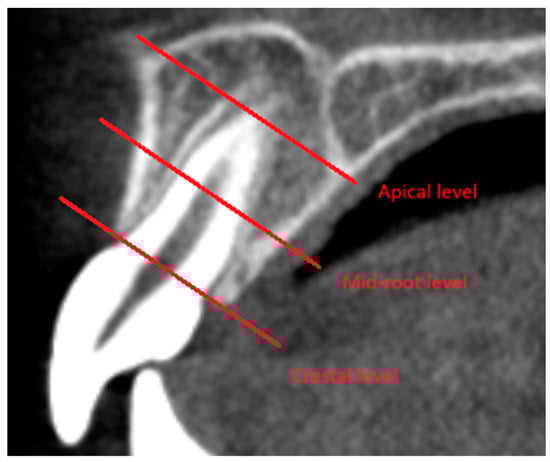

| Zheng Y. et al., 2022 [14] | N = 72 (F = 72) | G1 (minor) = 36 G2 (adult) = 36 | G1 (minor) 11–16 years old G2 (adult) 18–35 years old | Bimaxillary protrusion with class I malocclusion | Extraction of four first Premolars, Self-ligating brackets | Pre- and post-treatment CBCT and late cephalograms | Changes of the alveolar bone thickness at the crestal, mid-root and apical third in the central incisor (adults): Labial: La3: 0.16 ± 0.44 La6: 0.09 ± 0.46 La9: 0.26 ± 0.85 Palatal: P3: −1.48 ± 0.79 P6: −1.70 ± 1.41 P9: −1.59 ± 2.67 Changes of the alveolar bone thickness at the crestal, mid-root and apical third in the central incisor (minors): Labial: La3: 0.38 ± 0.47 La6: 0.29 ± 0.42 La9: 0.32 ± 0.70 Palatal: Minors: P3: −0.88 ± 1.21 P6: −0.82 ± 1.82 P9: −0.33 ± 2.25 |

| Eksriwong et al., 2021 [17] | N = 17 (F = 17) | G1 = 17 | 18 to 30 years old | on | Extraction of the maxillary first premolars, Incisor retraction was performed using T-loop | Pre- and post-treatment CBCT | Alveolar Bone changes (CT0 -CT1) at crestal, mid-root and apical Level of the maxillary Incisor Roots: Labial: Crestal: −1.3 ± 1.1 Mid-root: −0.9 ± 1.5 Apical: −0.8 ± 0.9 Palatal: Crestal: −0.2 ± 0.5 Mid-root: −0.1 ± 0.7 Apical: −0.2 ± 0.4 |

| Zhang C. et al., 2022 [16] | N = 63 (M = 10, F = 53) | G1 = 63 | Mean ± SD 24.41 ± 5.80 years 18–42 years old | on | Extraction of four first premolars | Pre- and post-treatment CBCT | The thickness changes in the maxillary alveolar bone at crestal, mid-root, and apical levels: Labial: A1: T0: 1.38 ± 0.76 T1: 1.13 ± 0.74 A2: T0: 1.71 ± 0.74 T1: 1.39 ± 0.77 A3: T0: 3.24 ± 1.36 T1: 2.75 ± 1.10 Palatal: B1: T0: 1.42 ± 0.69 T1: 1.41 ± 0.82 B2: T0: 2.91 ± 1.50 T1: 2.56 ± 1.58 B3: T0: 7.12 ± 1.76 T1: 6.74 ± 2.13 |

| Mao et al., 2020 [19] | N = 38 (M = 7, F = 31) | G1 = 38 | 15–33 years old Mean age 19.52 years | Bimaxillary protrusion with class I malocclusion | Interactive self-ligating brackets, retraction using TADs | Pre- and post-treatment CBCT | The thickness changes in the maxillary alveolar bone at the crestal, mid-root, and apical third: Labial: Crestal: T0: 0.8 ± 0.3 T1: 0.8 ± 0.3 Mid-root: T0: 0.7 ± 0.2 T1: 0.9 ± 0.4 Apical: T0: 0.9 ± 0.3 T1: 1.0 ± 0.6 Palatal: Crestal: T0: 1.6 ± 0.4 T1: 0.7 ± 0.9 Mid-root: T0: 2.9 ± 0.8 T1: 2.2 ± 1.4 Apical: T0: 4.4 ± 1.4 T1: 4.2 ± 1.8 |

| Wang et al., 2021 [20] | N = 34 (M = 12, F = 22) | G1 = 34 | Mean ± SD 14.29 ± 1.24 years | Bimaxillary protrusion | Extractions of the four first premolars, miniscrews for maximum anchorage | Pre- and post-treatment CBCT | Comparison of mean labial and lingual alveolar bone thickness at T1 (pre-treatment), T2 (post-treatment) and T3 (retention phase) of the central incisor: Labial: Cervical level: T1: 1.53 ± 0.32 T2: 1.63 ± 0.57 T3: 1.61 ± 0.59 Middle level: T1 1.84 ± 0.50 T2: 1.95 ± 1.02 T3: 1.74 ± 0.52 Apical level: T1: 4.06 ± 1.35 T2: 4.07 ± 1.94 T3: 3.78 ± 1.31 Palatal: Cervical level: T1: 2.66 ± 0.77 T2: 1.88 ± 1.01 T3: 2.15 ± 0.60 Middle level: T1: 4.49 ± 1.58 T2: 3.75 ± 1.88 T3: 3.86 ± 1.34 Apical level: T1: 7.93 ± 1.87 T2: 7.33 ± 2.21 T3: 7.14 ± 1.74 |